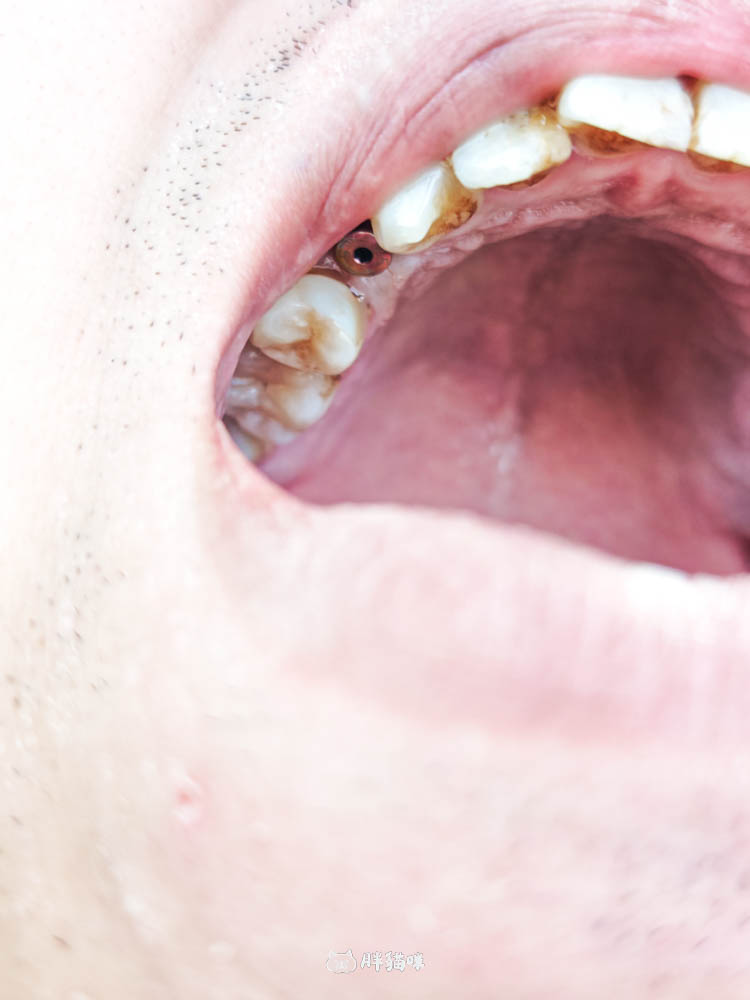

結果勒!他吐出來一看,才發現那塊「硬硬的東西」根本不是薯條,是:他自己的牙齒😱

雖然只斷了一半,但因為牙根還卡在裡面,狀況有點複雜,缺牙這個問題馬上就變成我們人生的頭等大事了!

植體植入的步驟大概就是~醫生先把萊肯的斷牙牙根拔除,接著植體就直接放進去,讓它跟骨頭開始骨整合。因為拔牙會有一個坑洞,醫生在裡面填補了骨粉,這個骨粉未來就會變成萊肯骨頭的一部分。

最後,醫生會縫合傷口,讓傷口變得很小,說兩週後回來拆線就好。